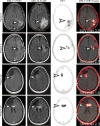

High-grade gliomas (World Health Organization grade III-IV) are highly lethal primary brain tumors. Imaging modalities, including MRI and FDG PET, provide a limited ability to differentiate treatment effects (such as radiation necrosis) from recurrent or residual tumor. As the first step in validating the applicability of prostate-specific membrane antigen (PSMA)-targeted imaging in high-grade gliomas, we evaluated the ability of the PSMA-targeted small molecule [F]DCFPyL (2-(3-(1carboxy-5-(6-[F]fluoro-pyridine-3-carbonyl)-amino]-pentyl)-ureido)-pentanedioic acid) to image high-grade gliomas in a series of 3 prospectively recruited patients. We found [F]DCFPyL binds PSMA in the neovasculature of glioblastoma multiforme and tumor cells of anaplastic astrocytoma.